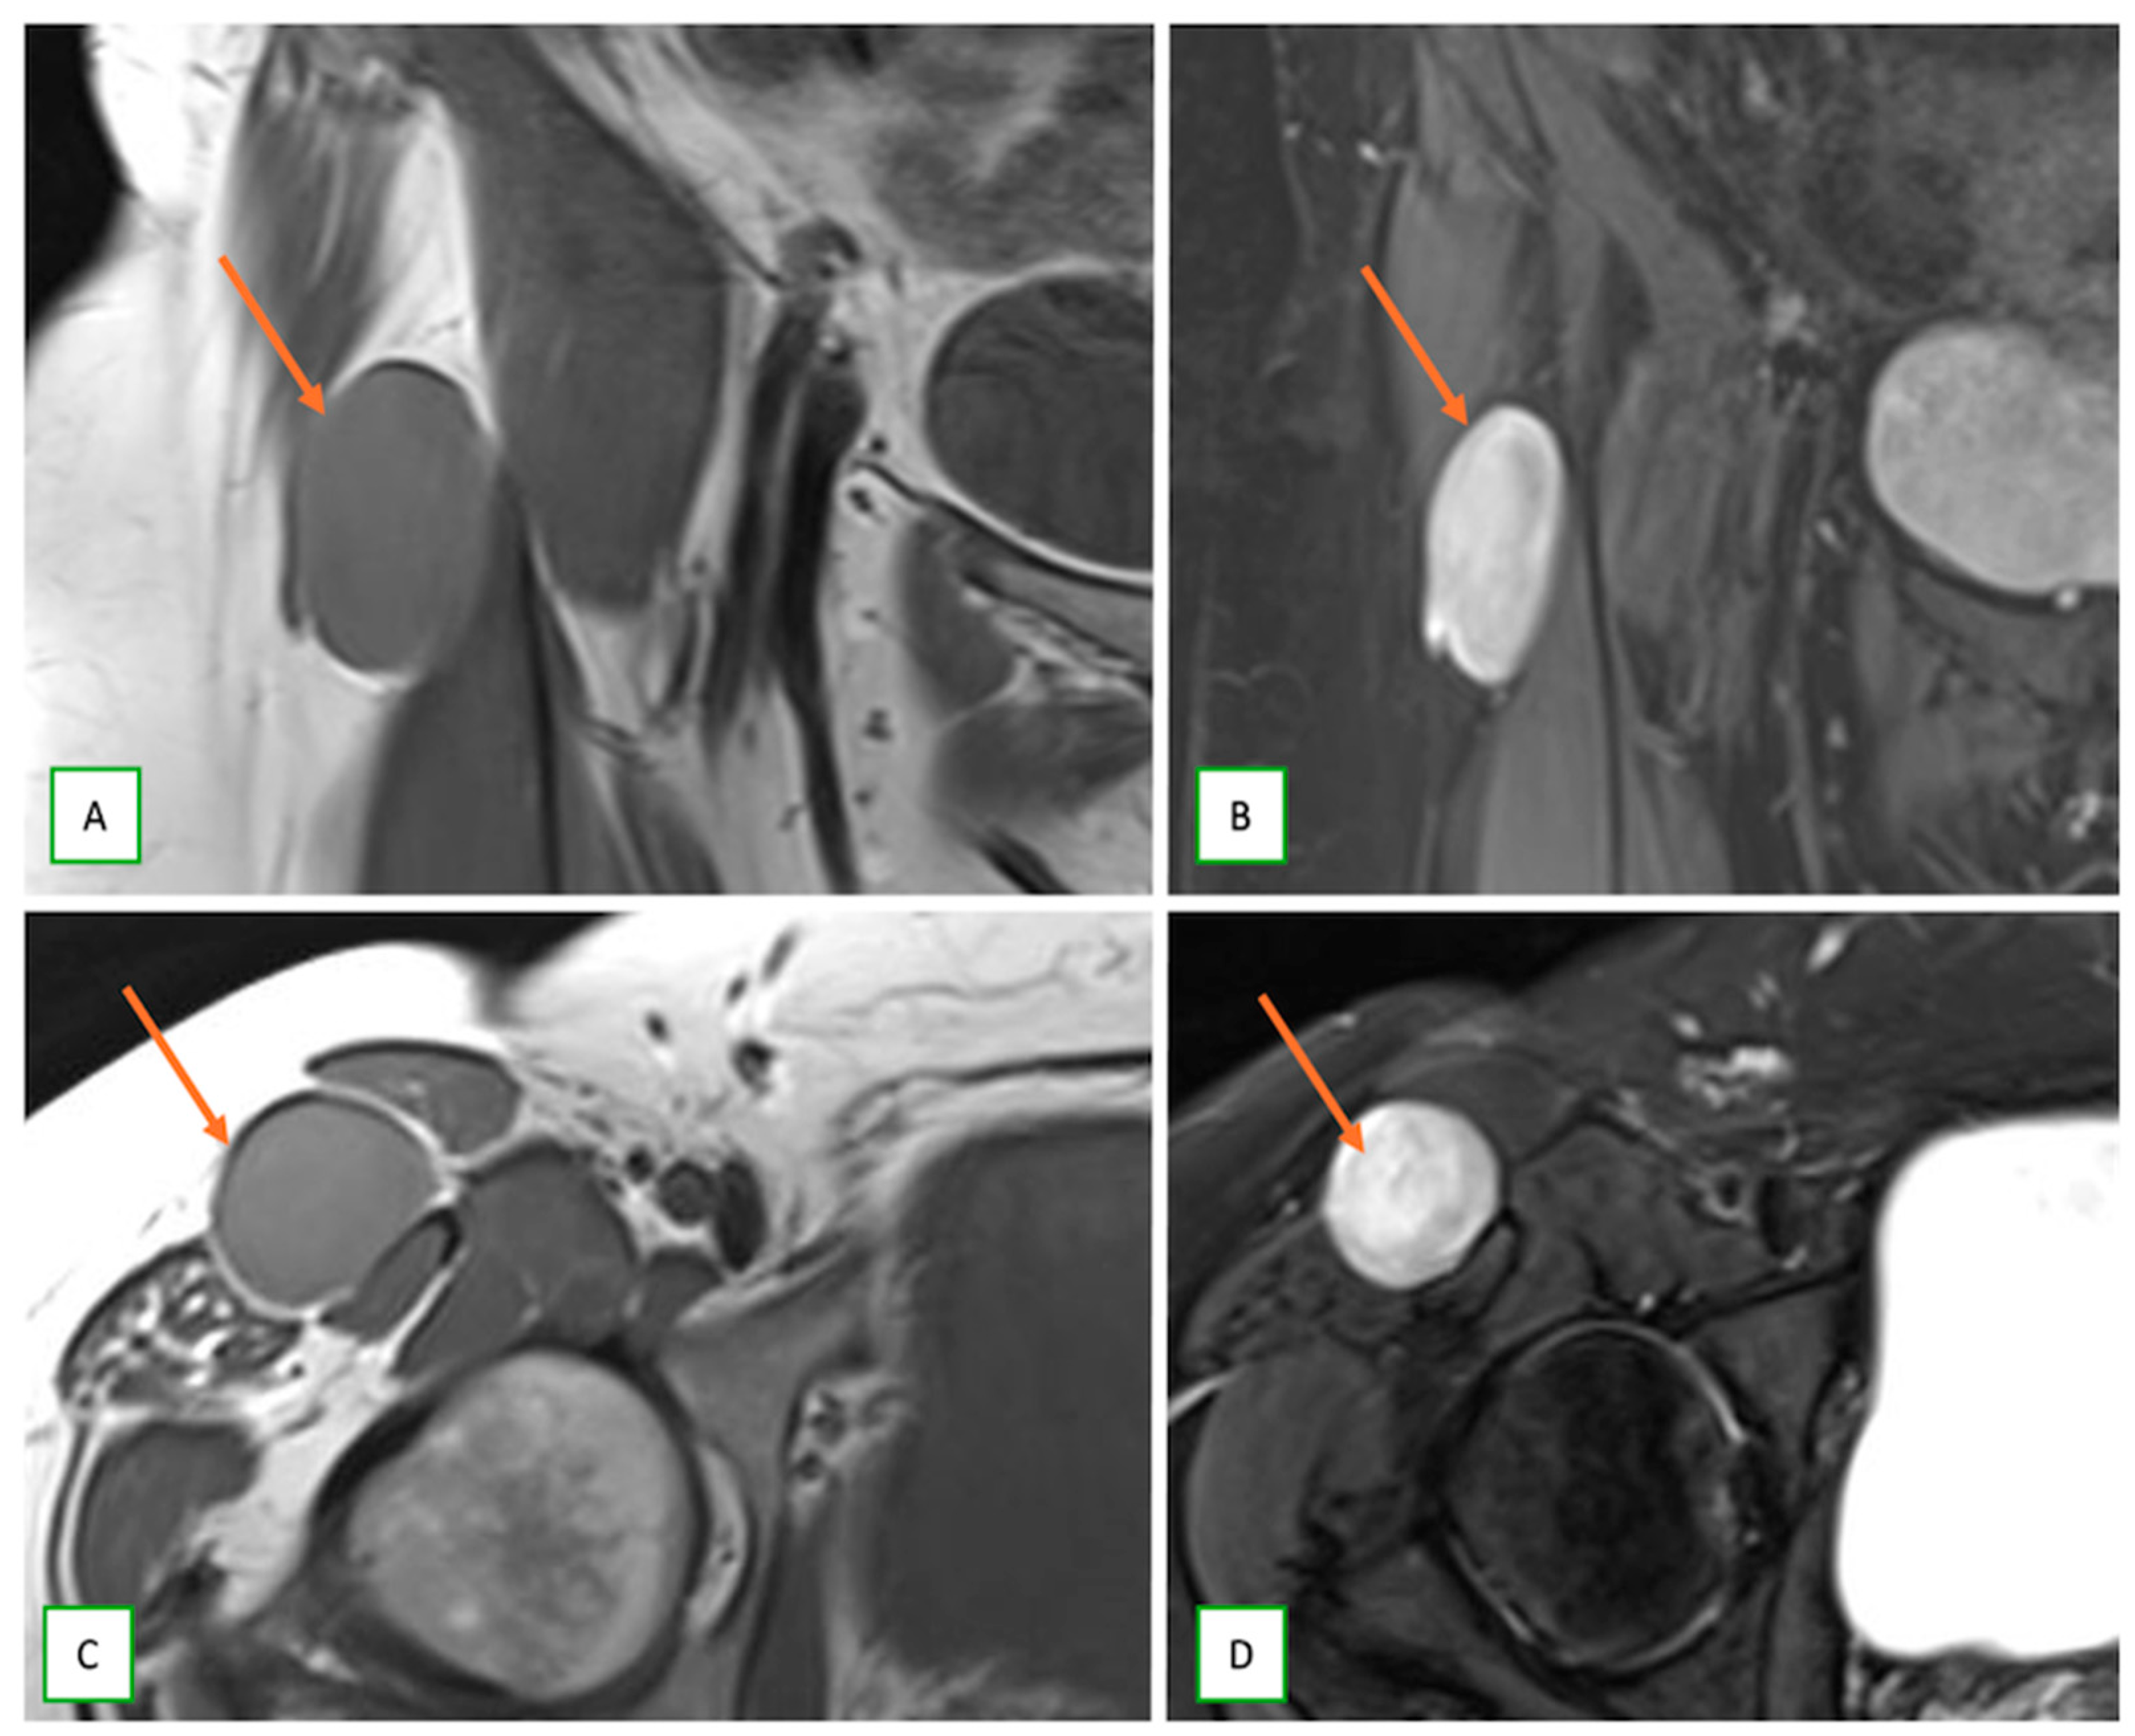

- Benign triton tumors, or neuromuscular choristomas, are rare congenital lesions with a mix of neural and striated muscle elements, usually appearing as fusiform nerve enlargements with heterogeneous signals on MRI and often mimicking an aggressive lesion. They typically present in the first two decades (Figure 18).